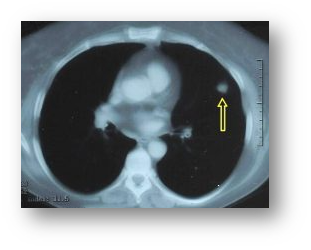

폐결절을 정확히 진단하기 위해서는 CT 검사가 필수적이에요. 저선량 흉부 CT는 방사선 노출을 최소화하면서도 결절을 발견할 수 있어요. 특히 정기 검진이나 추적 관찰에 많이 사용된답니다.

필요에 따라 조영제를 사용하는 CT 검사도 있어요. 조영제를 사용하면 결절의 혈류나 조직 특성을 더 자세히 알 수 있어요. 하지만 조영제 알레르기가 있는 분들은 주의해야 해요.